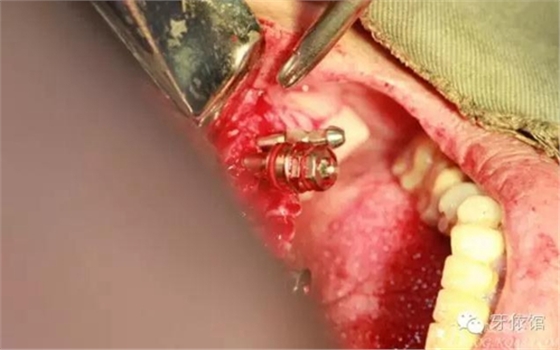

降低骨高度,左右1,2骨寬度嚴(yán)重不足,決定將前牙2——2區(qū)間植體植在切牙孔內(nèi)

這個(gè)角度看1,2牙位骨寬度是不是很薄??jī)H2mm

用擴(kuò)孔鉆去除切牙孔內(nèi)神經(jīng)纖維和血管

切牙壓孔內(nèi)植入植體,扭力50n